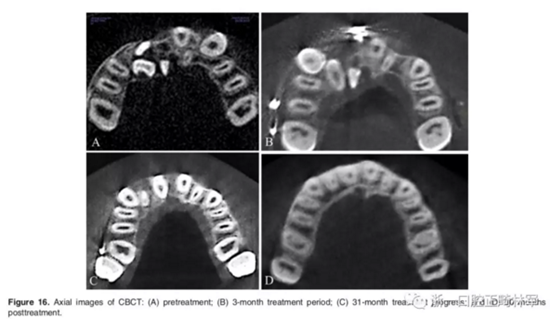

全景X片及CBCT示:11-13復雜阻生,上頜前牙區(qū)牙槽骨水平不足;11阻生,遠中旋轉(zhuǎn)90°,牙冠朝向腭側,根尖位于鼻底、前鼻棘皮質(zhì)骨內(nèi),牙根形態(tài)彎曲;12、13不完全易位,12位置偏腭側,13位置偏舌側,12的牙根形態(tài)也較彎曲。

影像學:頭顱側位片示:矢狀向和垂直向骨骼發(fā)生變化(ANB角,3°;SN-MP,51°);上頜切牙略前傾(U1-SN,106°),與下頜切牙一致(IMPA,75°);病人的面部輪廓得以保持。全景片示:由于牙齒萌出,上前牙區(qū)垂直向牙槽骨水平增加;雖然前牙牙根較彎曲,但其平行度仍可,且無明顯的牙根吸收。CBCT示:前牙唇側骨質(zhì)連續(xù)性改善,牙根唇側支持組織變好,牙槽骨高度、厚度均有增加,但轉(zhuǎn)矩的改變一定程度上導致了局部應力的增大。

2年隨訪:咬合關系保持穩(wěn)定,無明顯復發(fā),下頜有一定晚期生長趨勢;前牙牙齦外形、牙冠高度無明顯變化;唇側牙槽骨高度、厚度均保持良好。